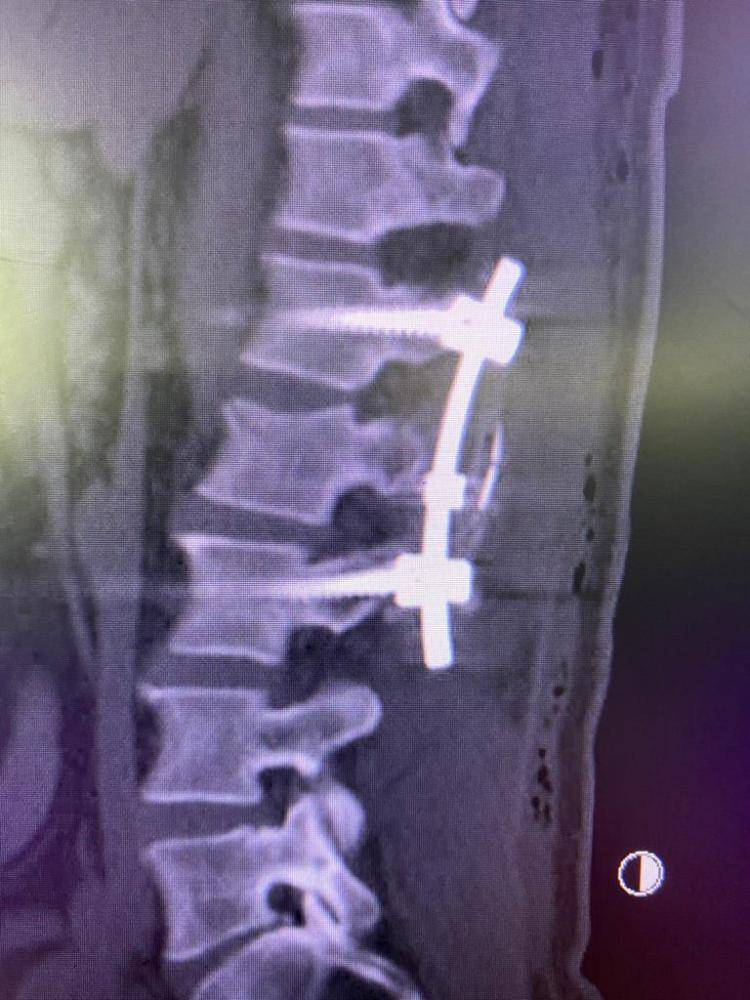

وفي التفصيل كانت الحالة الأولى لمقيم في العقد الثالث كان يعاني من كسر في الفقرة الثانية عشرة الصدرية ضاغط على القناة الفقرية وغير مستقر، وأجريت له العملية لتثبيت الفقرات الصدرية من الفقرة العاشرة وحتى الثانية القطنية بمسامير وشرائح.

كما تم إجراء عملية ثالثة لمقيم سوري في العقد الرابع بتثبيت الفقرات القطنية بمسامير من الفقرة الأولى وحتى الرابعة بعد تعرضه لكسر في الفقرة الثانية القطنية.

وفي حالة أخرى لمقيم في العقد الرابع كان يعاني من كسر في الفقرة الثانية عشرة الصدرية ضاغط على الحبل الشوكي والقناة الفقرية، قرر الفريق الطبي إجراء عملية تثبيت الفقرات من العاشرة الصدرية وحتى الثانية القطنية مع إزالة الضغط على القناة الفقرية الثانية عشرة. حيث تكللت جميع العمليات بالنجاح.